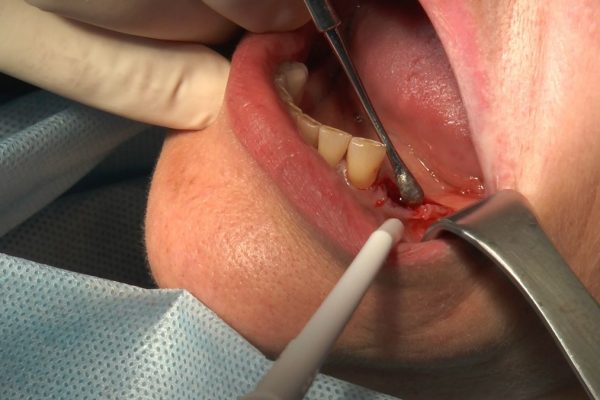

W ostatni weekend czerwca 2018 roku kursanci II Sezonu Preludium Implantologii odbyli piątą, finałową sesję, która w całości podporządkowana była praktyce. W ciągu dwóch dni zabiegowych Lekarze uczestniczący w szkoleniu przeprowadzili szereg zabiegów pod kierunkiem dr n.med. Violetty Szycik. Wszczepili 17 implantów oraz przeprowadzili ekstrakcje i zabiegi regeneracyjne kości. Zabiegi były wykonywane także w sedacji dożylnej z udziałem specjalisty anestezjologii i intensywnej terapii dr Jolanty Grzybowskiej. Preludium implantologii to nowy program edukacyjny dla adeptów implantologii stomatologicznej, którego celem jest wprowadzenie do implantologii poprzez pozyskanie wiedzy w szerokim zakresie i uwzględnieniem szczegółów mających decydujące znaczenie dla powodzenia leczenia implantologicznego. Ale tak jak wszystkie szkolenia w Instytucie Vivadental, w tym wiodące Practiculum Implantologii, zorientowane jest na praktyce i samodzielnym wykonywaniu zabiegów pod kierunkiem Mentora. To najlepsza edukacja w medycynie zabiegowej, a zarazem najlepszy start do implantologii.